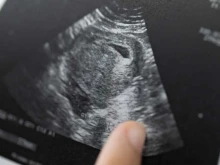

An unborn baby at 20 weeks.

Alabama outlaws abortion, setting up Supreme Court Roe v. Wade challenge

May 14, 2019

Alabama Gov. Kay Ivey signed into law Wednesday a bill that will outlaw nearly all abortion in the state. The... Read more